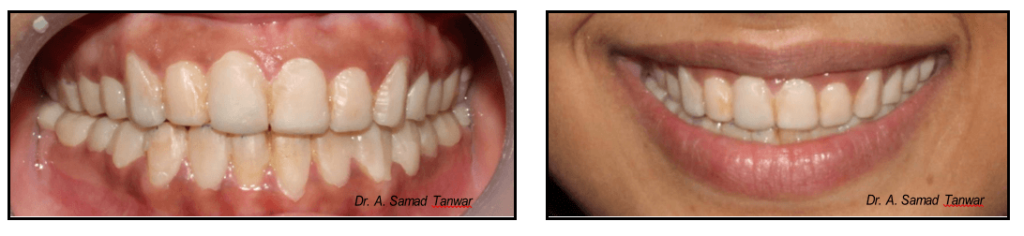

Patient reported to the Department of Prosthodontics with a chief complaint of discoloured teeth

The intraoral photographs of the patient reveals yellowish discolouration of teeth with generalized

On thorough clinical examination it was found that patient has enamel hypoplasia.